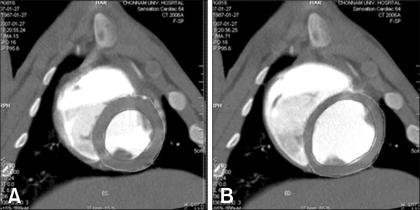

Pigs are the most likely source animals for cardiac xenotransplantation. However, an appropriate method for estimating the cardiac function of micropigs had not been established. Computed tomography (CT) analysis aimed at estimating cardiac function and assessing the coronary arteries has not been carried out in micropigs. This study determined the feasibility of evaluating cardiac function in a micropig model using multidetector row computed tomography (MDCT) and compared the cardiac function values with those of conventional pigs. The mean age of the conventional pigs and micropigs was approximately 80 days and approximately 360 days, respectively. The mean body weight in the conventional pigs and micropigs was 29.70 +/- 0.73 and 34.10 +/- 0.98 kg, respectively. Cardiac MDCT detected ejection fractions of 52.93 +/- 3.10% and 59.00 +/- 5.56% and cardiac outputs of 1.46 +/- 0.64 l/min and 1.21 +/- 0.24 l/min in conventional pigs and micropigs, respectively. There were no significant differences in cardiac function between conventional pigs and micropigs in the reconstructed CT images. There were also no differences in the coronary angiographic images obtained by MDCT. It is expected that the results of this study will help improve understanding of cardiac function in micropigs. The data presented in this study suggest that MDCT is a feasible method for evaluating cardiac function in micropigs.

猪是心脏异种移植最有可能的供体动物。然而,尚未建立一种合适的方法来评估小型猪的心脏功能。针对评估心脏功能和冠状动脉的计算机断层扫描(CT)分析尚未在小型猪中进行。本研究确定了使用多排探测器计算机断层扫描(MDCT)评估小型猪模型心脏功能的可行性,并将心脏功能值与传统猪的进行比较。传统猪和小型猪的平均年龄分别约为80天和约360天。传统猪和小型猪的平均体重分别为29.70±0.73千克和34.10±0.98千克。心脏MDCT检测到传统猪和小型猪的射血分数分别为52.93±3.10%和59.00±5.56%,心输出量分别为1.46±0.64升/分钟和1.21±0.24升/分钟。在重建的CT图像中,传统猪和小型猪的心脏功能没有显著差异。MDCT获得的冠状动脉造影图像也没有差异。预计本研究结果将有助于增进对小型猪心脏功能的了解。本研究提供的数据表明,MDCT是评估小型猪心脏功能的一种可行方法。